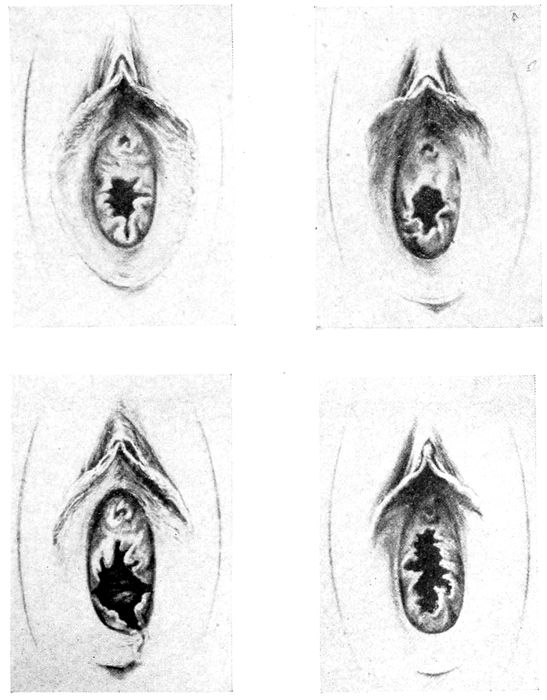

Fig. 7 A.—Varieties of hymen. (American Text Book.)